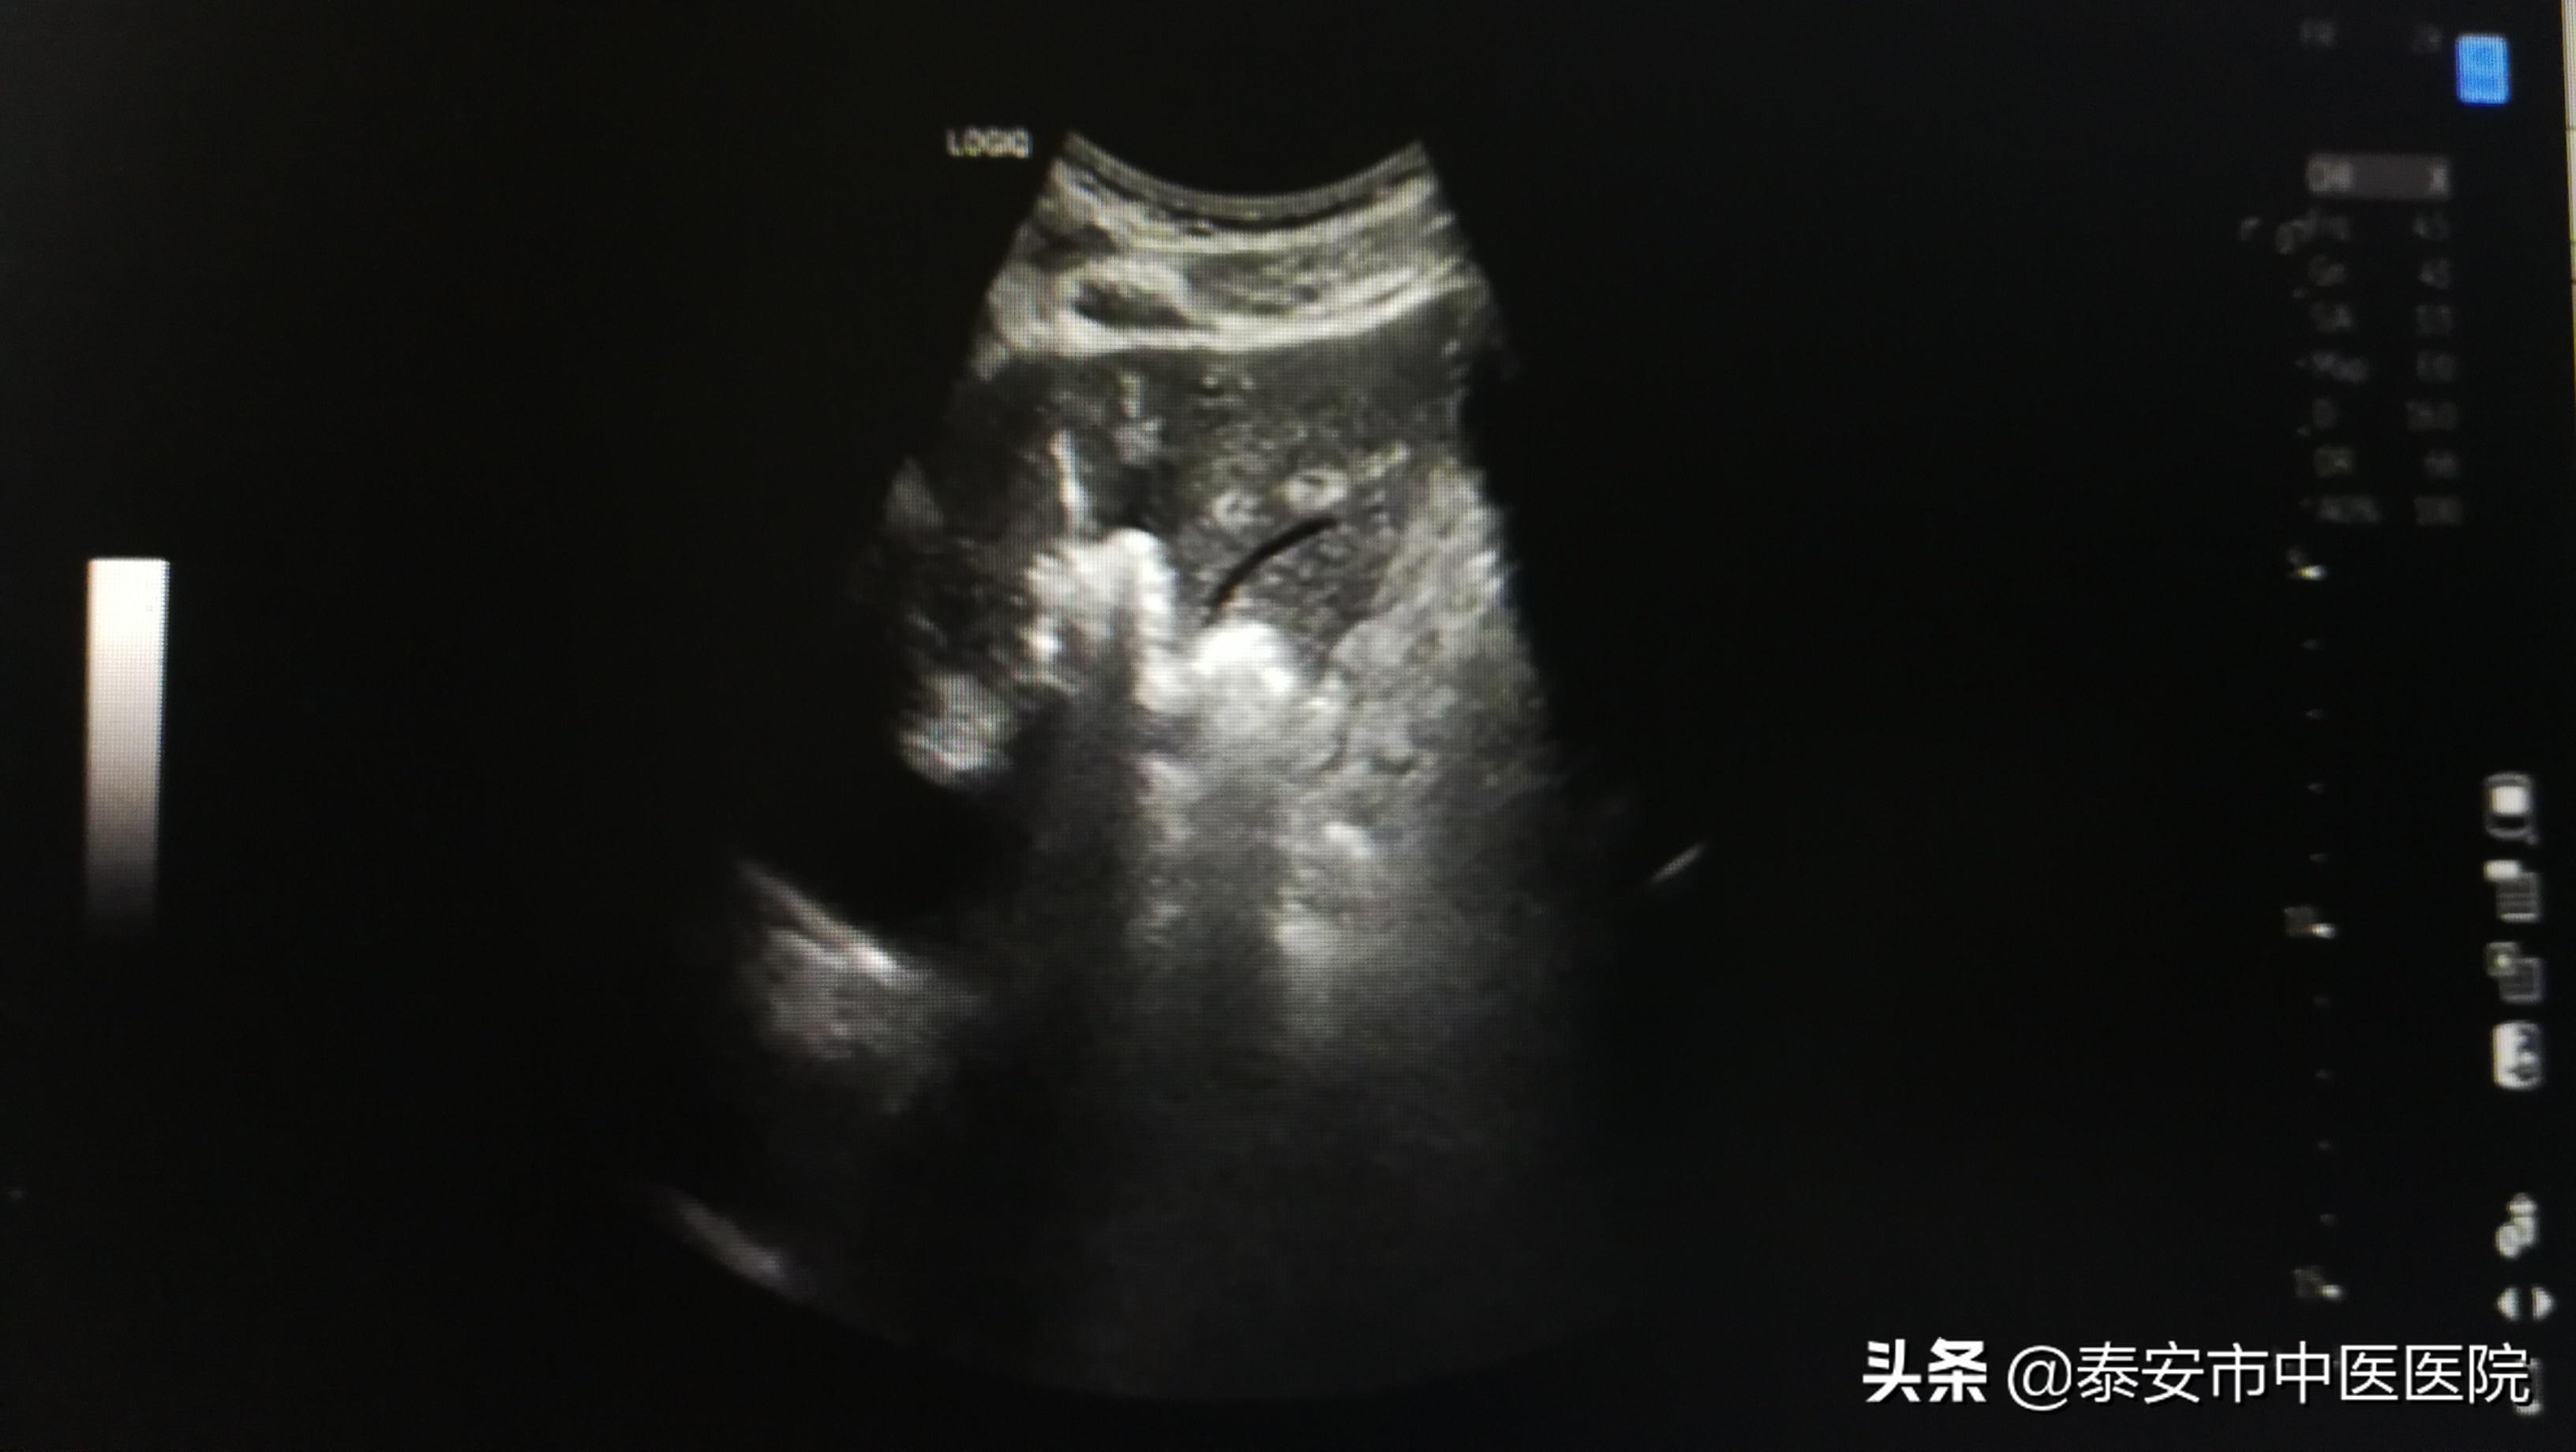

超声介入科特聘专家梁波教授会诊后,经与患者及家属充分沟通并同意后,决定在我院超声介入科行肝血管瘤超声引导下经皮穿刺微波消融术。术中,梁波教授基于深厚的超声功底和精准的穿刺技术,将微波消融针精准穿刺进入肿瘤内,施加微波加热治疗,10余分钟手术成功完成,术后伤口不足2mm。